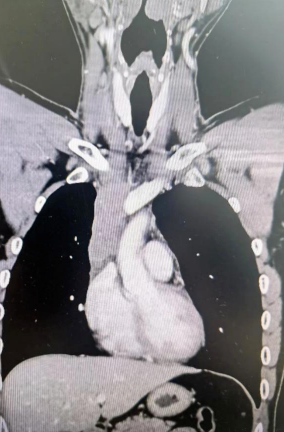

經(jīng)檢查發(fā)現(xiàn)患者前上縱隔腫瘤已經(jīng)完全侵犯了我們?nèi)梭w最主要的大靜脈之一——上腔靜脈,導致上腔靜脈回流嚴重受阻并導致由上腔靜脈起至左側(cè)無名靜脈、右側(cè)鎖骨下靜脈、右側(cè)頸內(nèi)靜脈等多根自上往下回流的靜脈阻塞,從而形成了廣泛的栓子,牢牢堵住了要流回心臟的血流,只能靠別的一些側(cè)支循環(huán)超負荷的工作,這也就是為什么孫先生脖子甚至是頭都明顯腫起來的原因。

4月30日,麻醉完成后,縱劈胸骨顯露右上縱隔腫瘤,發(fā)現(xiàn)腫瘤侵入上腔靜脈起始部,右鎖骨下靜脈及右頸內(nèi)靜脈血栓形成并向遠端延伸。劉志主任團隊將切口向右頸部延長,顯露右側(cè)頸內(nèi)靜脈至下頜角水平。張金洲副院長團隊經(jīng)股動靜脈和左無名靜脈建立體外循環(huán)。在阻斷左無名靜脈遠端后,李文海副院長團隊完整切除縱隔腫瘤及部分上腔靜脈、左無名靜脈、右鎖骨下靜脈和右頸內(nèi)靜脈切除。張金洲副院長團隊實施了無名靜脈近端、右鎖骨下靜脈和右頸內(nèi)靜脈內(nèi)血栓取出術(shù),并完成了左無名靜脈、右頸內(nèi)靜脈和右鎖骨下靜脈的人工血管置換手術(shù)。歷時6小時,三個外科團隊在麻醉科柴偉主任團隊、體外循環(huán)團隊以及食管超聲和手術(shù)室協(xié)作下,手術(shù)獲得成功。

術(shù)后患者經(jīng)過心外監(jiān)護室和胸外監(jiān)護室的接力治療,目前患者恢復順利,顏面部腫消失。復查增強CT三條人工血管通暢。